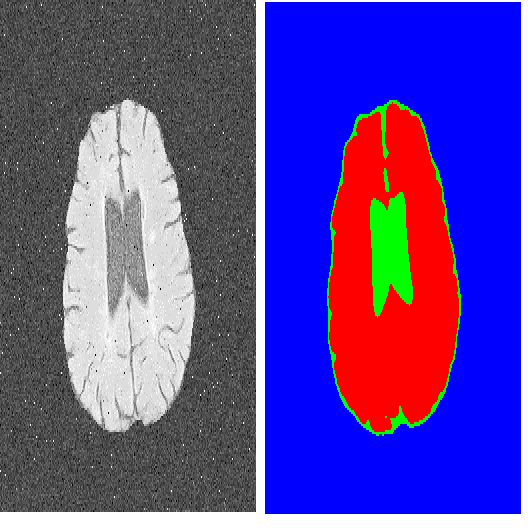

Deep Convolutional Neural Networks (DCNNs) are used extensively in biomedical image segmentation. However, current DCNNs usually use down sampling layers for increasing the receptive field and gaining abstract semantic information. These down sampling layers decrease the spatial dimension of feature maps, which can be detrimental to semantic image segmentation. Atrous convolution is an alternative for the down sampling layer. It increases the receptive field whilst maintains the spatial dimension of feature maps. In this paper, a method for effective atrous rate setting is proposed to achieve the largest and fully-covered receptive field with a minimum number of atrous convolutional layers. Furthermore, different atrous blocks, shortcut connections and normalization methods are explored to select the optimal network structure setting. These lead to a new and full-scale DCNN - Atrous Convolutional Neural Network (ACNN), which incorporates cascaded atrous II-blocks, residual learning and Fine Group Normalization (FGN). Application results of the proposed ACNN to Magnetic Resonance Imaging (MRI) and Computed Tomography (CT) image segmentation demonstrate that the proposed ACNN can achieve comparable segmentation Dice Similarity Coefficients (DSCs) to U-Net, optimized U-Net and hybrid network, but with significantly reduced trainable parameters due to the use of full-scale feature maps and therefore computationally is much more efficient for both the training and inference.